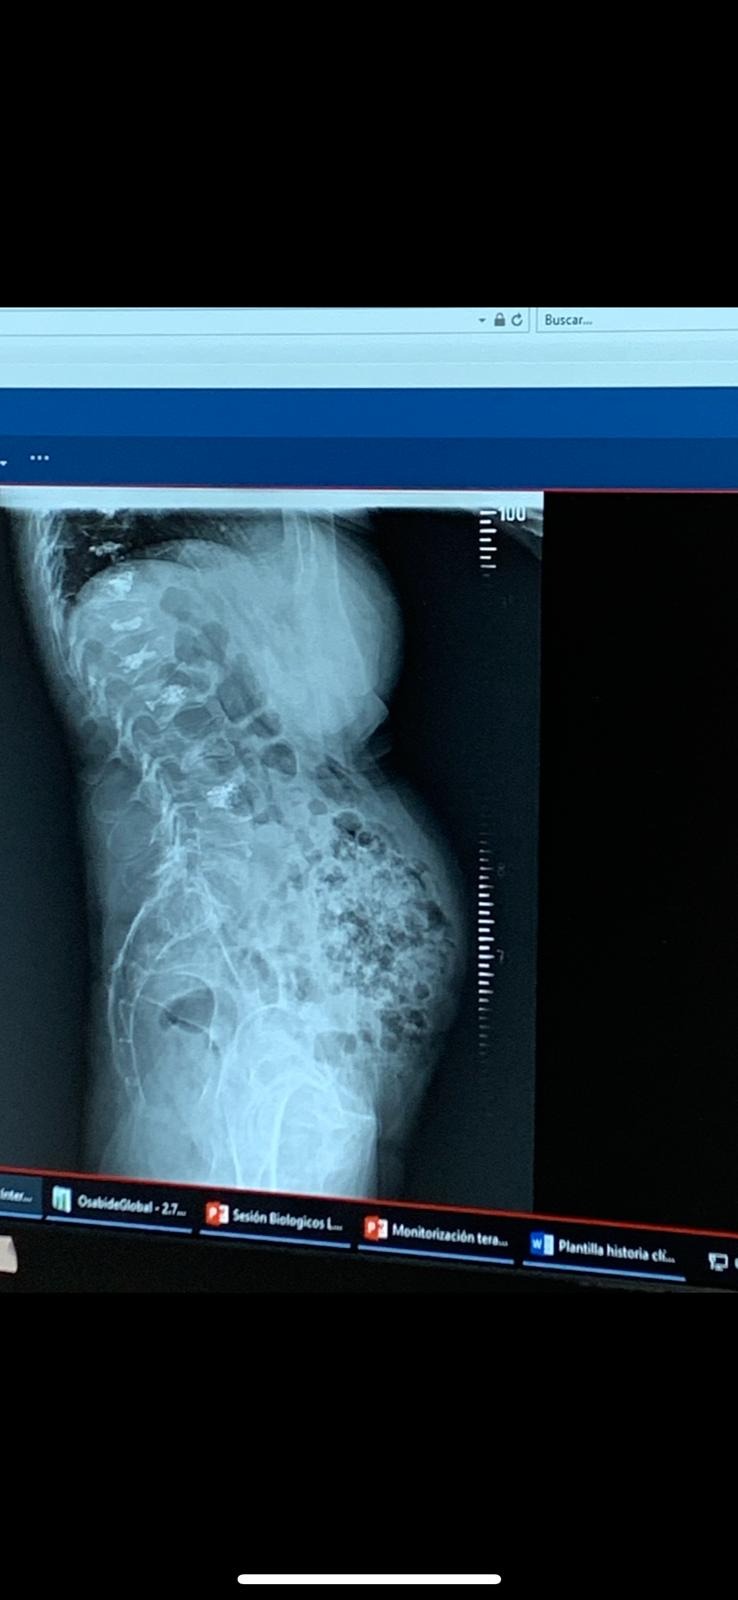

Para poner recta la mitad de la columna q esta detras los intestinos ya que tengo, HIPERLORDOSIS LUMBAR Y DORSAL SEVERA, CIFOSIS(Alteraciones significativas de la estática espinal con hipercifosis dorsal e hiperlordosis lumbar.)

Adjunto informe del neurocirujano traumatologo doctor António Luis Mostaza. TeleRadiografías, imagenes del antes y ahora tras perder 8-10cms de altura mínimo :(

A rare and severe spinal collapse has left my body broken. I have severe hyperlordosis and severe kyphosis. (I’m attaching images.)

My spine is deformed, with crushed and fractured vertebrae that are compressing my organs. My diaphragm and intestines are being pushed outward, making me look pregnant, but the reality is far more painful.